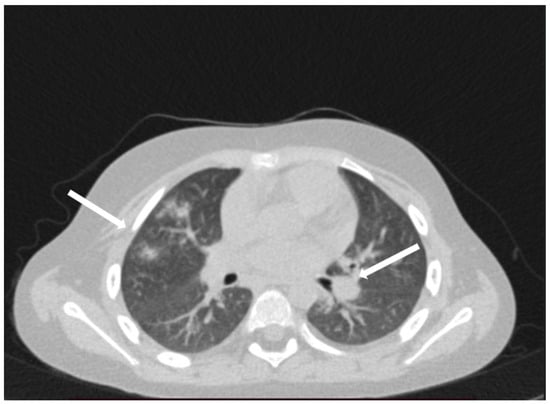

The patient was hospitalized in the Pediatric Clinic I for 3 weeks, being closely monitored (seriated clinical exam, laboratory tests, and echocardiography). The patient’s evolution gradually became favorable, and he was discharged with the recommendation to continue antiplatelet therapy and low-dose oral steroids. However, 4 days after discharge, the patient presented to the Emergency Department with altered general condition, respiratory distress, and fatigue. Laboratory tests revealed leukocytosis (27.720 × 103/μL), with neutrophilia (22.970 × 103/μL), thrombocytosis (491 × 103/μL), monocytosis (2.180 × 103/μL), and elevated inflammatory markers (CRP > 180 mg/L, ESR 43 mm/h), while urine analysis and cardiac enzymes were within normal limits. In the emergency department, a chest X-ray was performed which pointed out diffuse peribronchovascular infiltrates and inferior interclavicular hilar infiltrates (Figure 1). Given the influenced general condition and the presence of respiratory failure (oxygen saturation of 90%), along with the findings of the chest X-ray, we decided also to perform pulmonary computed tomography (CT), which identified ground-glass opacities with subpleural disposition adjacent to the mediastinum, in the upper lobes at the apical and posterior segments of the right lung, and at the apicoposterior segment of the left lung. Additionally, in the lower pulmonary lobes, opacities were observed in the bilateral posterior segments, left anteromedial, and right medial segments, indicative of possible pulmonary hypertension/incipient pulmonary edema/acute respiratory distress syndrome (ARDS) (Figure 2 and Figure 3). Pulmonary hypertension and pulmonary edema were ruled out based on clinical findings, cardiac examination, and normal cardiac enzymes. Based on all these findings, we considered pneumonia in the context of immunosuppression and we performed several tests to identify the possible etiology, finding elevated positive anti-CMV IgM antibodies and increased IgG antibodies of CMV (967.9 U/mL), which were confirmed by subsequent repeated tests. Additionally, we found evidence of hepatocellular injury (ALT: 166 U/L; AST: 60.7 U/L) prompting intravenous hepatoprotective treatment and initiation of an unspecified immunomodulatory agent, inosine acedoben dimepranol, orally, at a dose of 50 mg/kg body weight per day. This approach was chosen due to limitations in specific antiviral therapy for the pediatric population.

Figure 1. Diffuse peribronchovascular infiltrates and inferior interclavicular hilar infiltrates (white arrows).